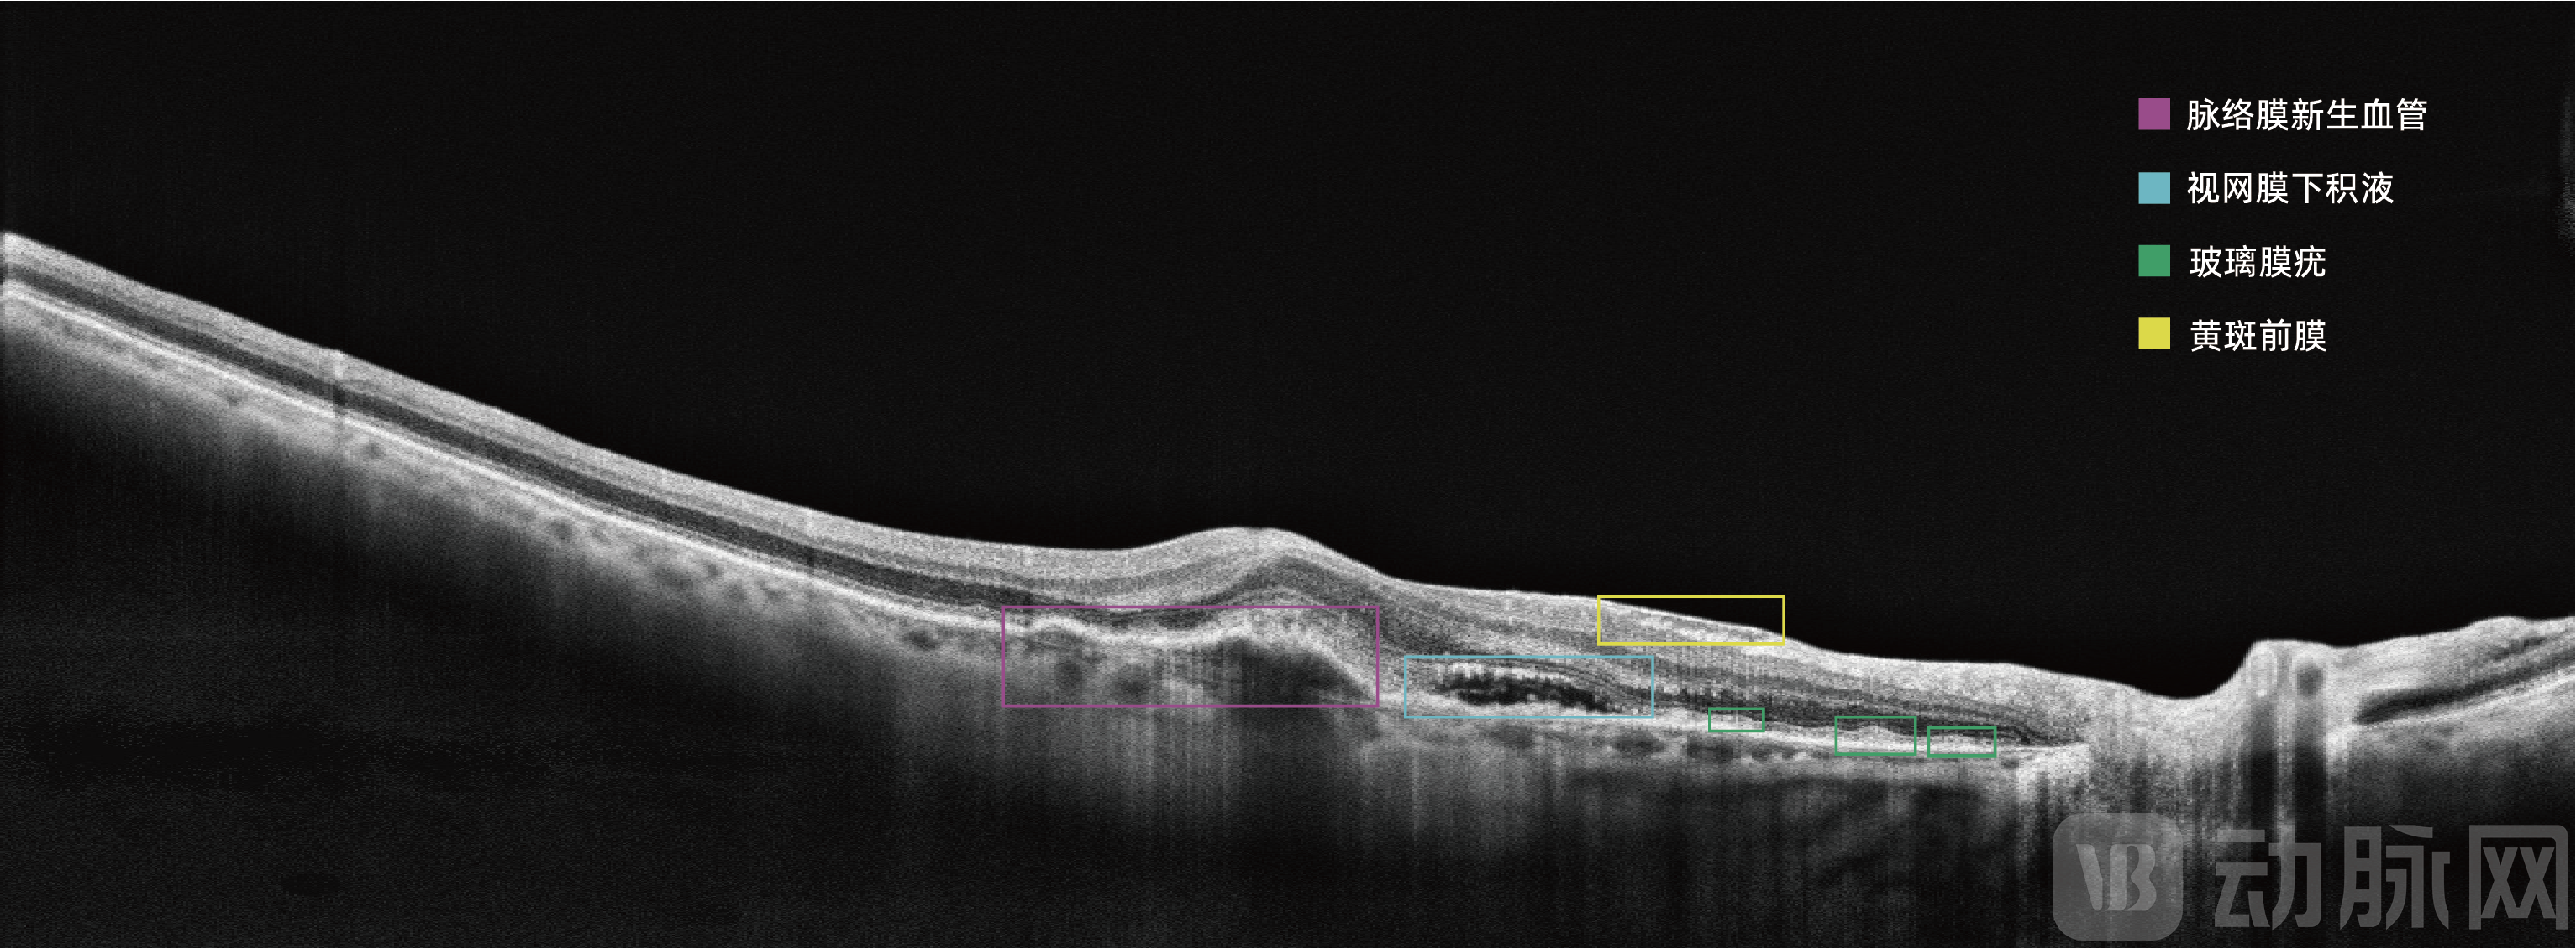

眼底彩照影像为视网膜二维图像,而OCT获取的是视网膜三维结构信息;OCT影像包含的视网膜结构层次信息丰富复杂,AI算法开发的难度较眼底彩照更大。比格威医疗基于OCT影像对年龄相关性黄斑变性(AMD)等十余种眼底疾病的分类、识别、病灶分割算法进行持续研究,取得一系列创新成果,在这一技术领域申请专利70余项,已获授权的发明专利达30余项。

2020年,比格威医疗共同完成的“智能医学影像分析及其临床诊断应用”获“吴文俊人工智能技术发明奖”一等奖。吴文俊人工智能科学技术奖由中国人工智能学会发起主办,被誉为“中国智能科学技术最高奖”。这也是吴文俊人工智能科学技术奖设立十年来首次将一等奖授予医学影像AI。目前,比格威医疗开发的眼科OCT影像辅助诊断软件MIAS 3000已经启动三类医疗器械注册证的检测报证工作,有望成为全球首款获批三类医疗器械注册证的眼科OCT影像辅助诊断系统。